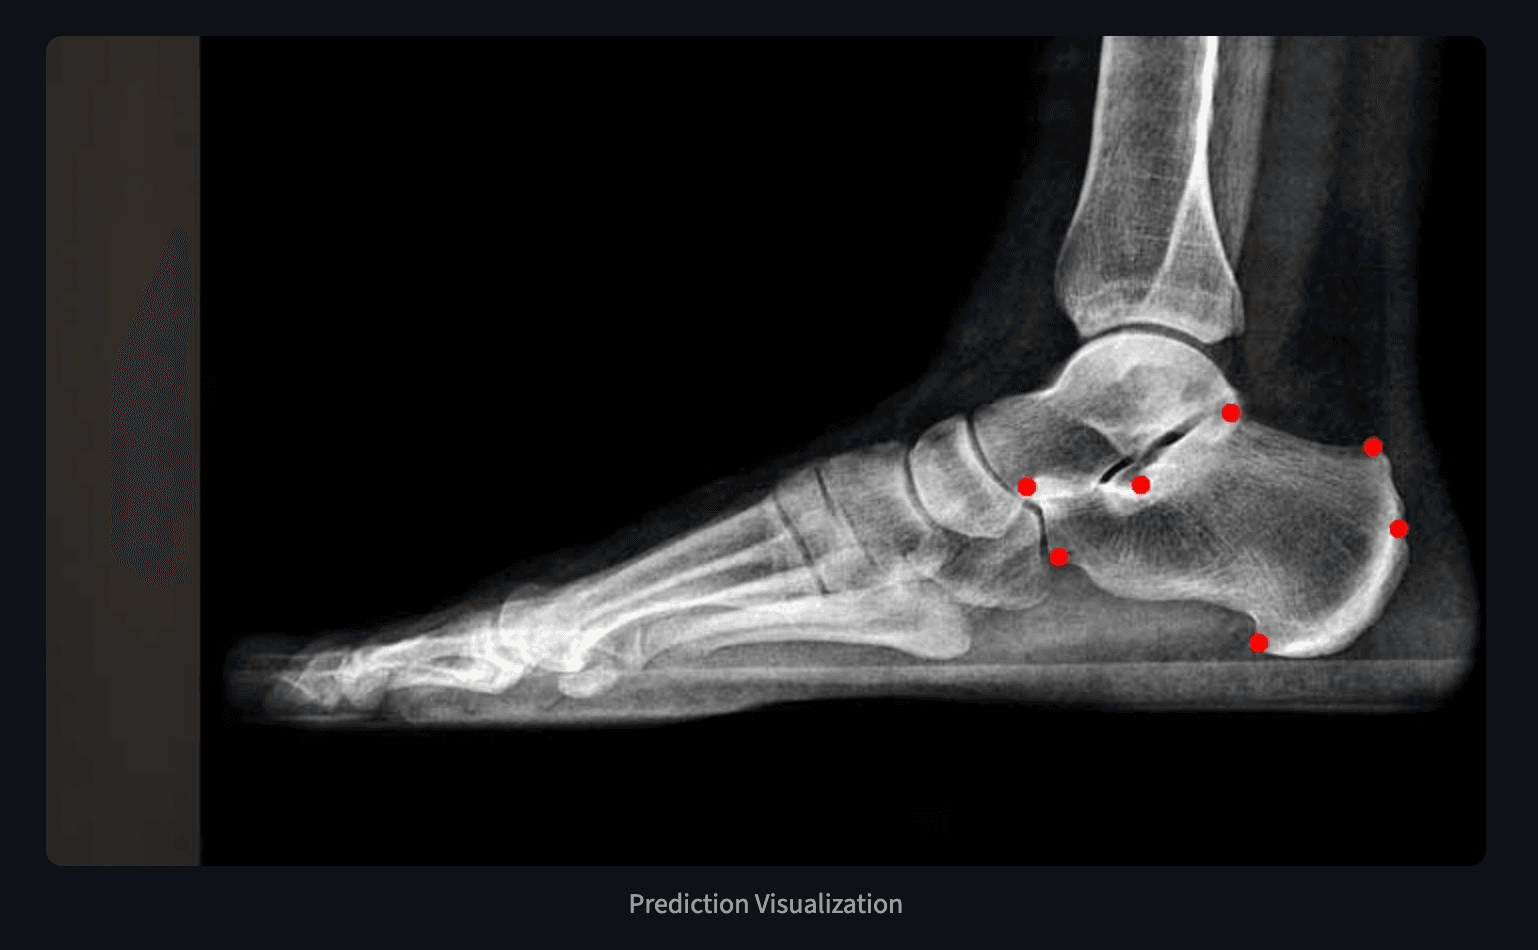

Automated Landmark Detection for Calcaneus

Streamlit app for automated calcaneus landmark detection using YOLO and GU2Net deep learning. 94% success detection rate with clinical interface.